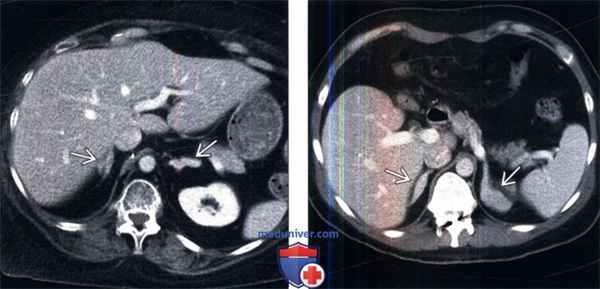

(Слева) На КТ с контрастированием у молодого мужчины с синдромом Кушинга визуализированы гиперстимулированные надпочечники вследствие эктопической (негипофизарной) секреции АКТГ. Наиболее распространенный источник эктопической секреции АКТГ— рак легкого, однако существуют и другие источники — тимус, кишечник и нейроэндокринные опухоли поджелудочной железы.

(Справа) На контрастной КТ мужчины 44 лет с врожденной гиперплазией надпочечников визуализированы увеличенные надпочечники. Коррекция заместительной терапии глюко-/минералокортикоидами увеличивает продолжительность жизни данных пациентов.